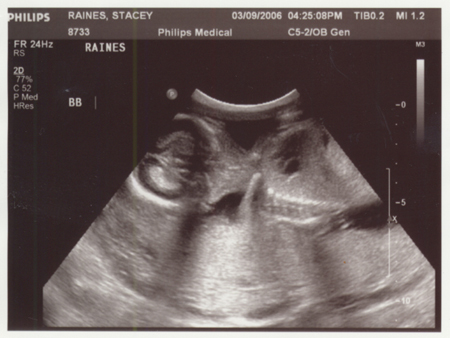

So have you figured out the answer. Excited or shocked? Well we are to.. very excited. So now we guess, this is the time to shock you. If you look close, these are not two pictures of the same.

Yep, TWINS!! And if you think trying to tell the difference above now is difficult, just wait until July/August when you can hold them.